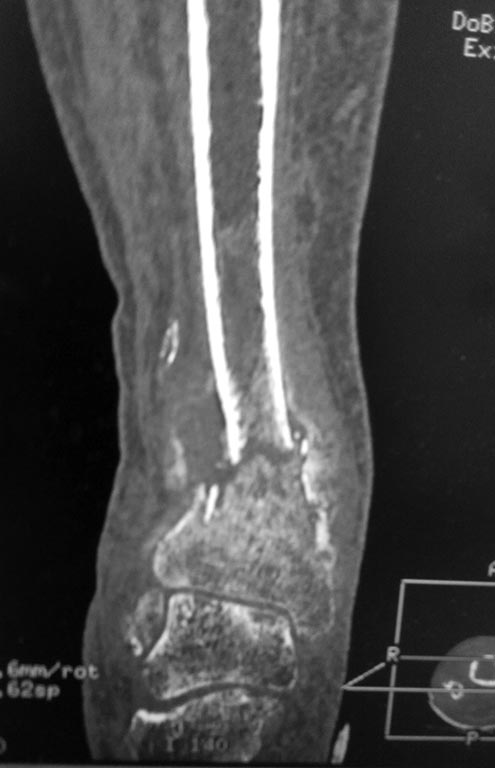

Перелом костей голени в нижней трети

Добрый день!Обратилась женщина 1958 г.р.Травма 08.09.16. Почувствовала боль в правой голени во время сна.

Лечилась амбулаторно с Ds: закрытый перелом костей правой голени в нижней трети без смещения. Повторную травму исключает. На контрольных Rg выявлено смещение отломков, признаки консолидации.

в анамнезе сахарный диабет I типа в течении 29 лет. лабильное течение. Диабетическая нефропатия. ХБП V ст. ХПН терминальная стадия. Хронический програмный гемодиализ. Ренальная остеодистрофия. Принимает лантус 6 Ед *1 раз в сутки. уровень сахара крови 12-15 ммоль\литр. Креатинин 543 мкмоль\литр, ЩФ 1270 Е\л.

А Вы то какой диагноз ставите? От чего сломалось? Ренальная остеодистрофия на фоне ХПН с гемодиализом? Диабетическая остеоартропатия? Пишете, что повторную травму исключает. Но и первичной не было. Последняя рентгенограмма (где перелом без смещения) когда была сделана? Сразу после обнаружения перелома? Там уже есть признаки консолидации. Есть ли признаки периферической нейропатии? Если не вдаваться в подробности, то можно думать об остеосинтезе двойного перелома наружной лодыжки (вероятно, уже срослась). И интрамедуллярном остеосинтезе большеберцовой кости.